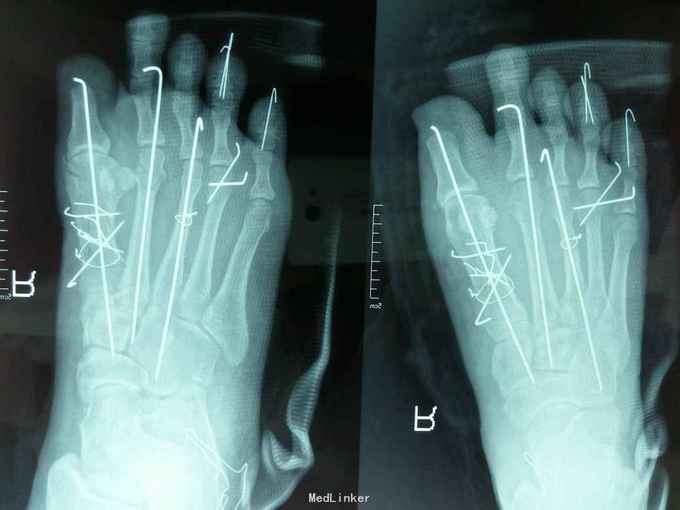

右足压砸伤 入院后完善相关住院及术前检查,急诊在腰麻下行‘右足清创、探查骨折复位内固定、踇趾残端修整术’,术后给予抗炎对症支持治疗。

术后病情平稳,愈合良好。